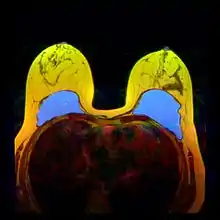

| تكبير الثدي في الجانبين بواسطة الوضع التحت العضلي ل 350 سم³ من الزرع من خلا انثناء أسفل الثدي |

وفقاً للجمعية الأمريكية لجراحي التجميل ، تكبير الثدي هي من أكثر العمليات الجراحية التجميلية الأكثر شيوعا في الولايات المتحدة. ووفقا للبيانات التي تم جمعها من قبل الجمعية الأمريكية لجراحة التجميل، لعام 2017 تم إجراء حوالي 300,000 عملية تكبير ثدي في الولايات المتحدة، وهو ارتفاع بنسبة 3 ٪ مقارنة بالسنة السابقة.